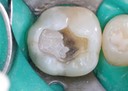

Joe Cha #3 prep